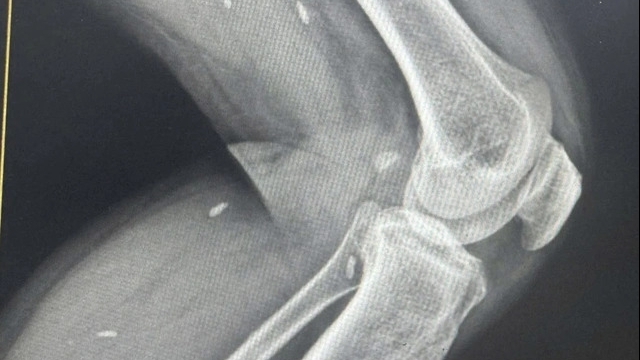

Sự thành công của phương pháp này đã được khẳng định trên ca phẫu thuật lấy u não cho chị L.T.B (45 tuổi ở Hợp Châu - Tam Đảo) vào ngày 28/9/2022 vừa qua. Người bệnh vào viện trong tình trạng đau đầu nhiều, chóng mặt. Qua thăm khám kiểm tra, chụp cộng hưởng từ (MRI), chụp cắt lớp vi tính (CT) sọ não, từ hình ảnh cho thấy người bệnh có khối u trong não, kích thước 12x12mm, tại vị trí thái dương đỉnh trên bên phải.

Với đội ngũ y bác sĩ có tay nghề cao, chuyên môn giỏi cùng với trang thiết bị hiện đại, sau 90 phút ca phẫu thuật đã diễn ra thành công, tốt đẹp. Khối u đã được loại bỏ hoàn toàn chỉ với đường mổ gọn (7cm), mảnh volet xương sọ nhỏ (3x4cm). Đường mổ và mảnh volet xương sọ của phương pháp này chỉ bằng một nửa so với phương pháp cũ.